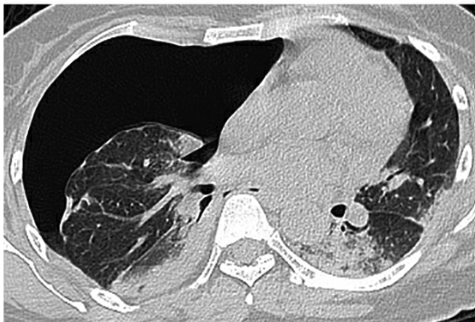

胸部CT(2018-04-02):右侧气胸,肺被压缩约60%;两肺多发斑片影,部分实变;双侧少量胸腔积液。病灶较外院胸部CT检查快速进展(图1)。

图1胸部CT:右侧气胸,肺组织压缩约60%;两肺多发斑片影,部分实变,以胸膜下为主;双侧少量胸腔积液;纵隔左移